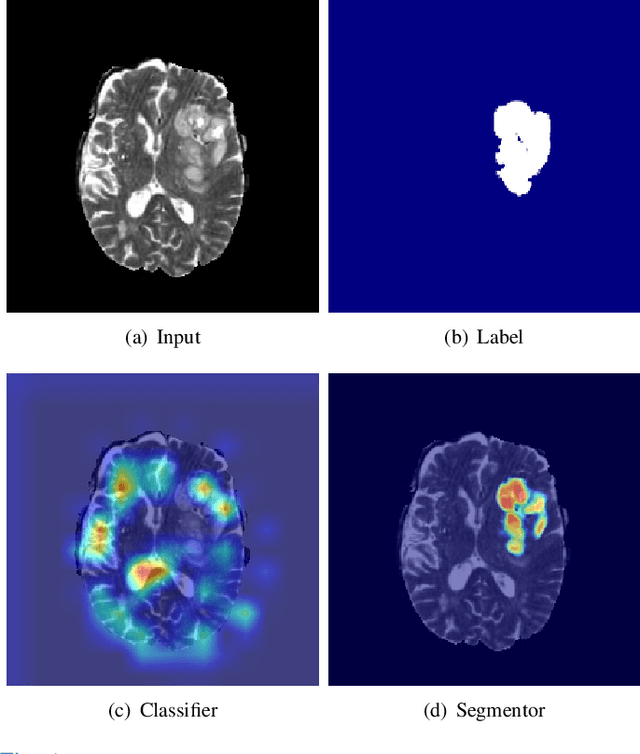

Abstract:Synthesizing a subject-specific pathology-free image from a pathological image is valuable for algorithm development and clinical practice. In recent years, several approaches based on the Generative Adversarial Network (GAN) have achieved promising results in pseudo-healthy synthesis. However, the discriminator (i.e., a classifier) in the GAN cannot accurately identify lesions and further hampers from generating admirable pseudo-healthy images. To address this problem, we present a new type of discriminator, the segmentor, to accurately locate the lesions and improve the visual quality of pseudo-healthy images. Then, we apply the generated images into medical image enhancement and utilize the enhanced results to cope with the low contrast problem existing in medical image segmentation. Furthermore, a reliable metric is proposed by utilizing two attributes of label noise to measure the health of synthetic images. Comprehensive experiments on the T2 modality of BraTS demonstrate that the proposed method substantially outperforms the state-of-the-art methods. The method achieves better performance than the existing methods with only 30\% of the training data. The effectiveness of the proposed method is also demonstrated on the LiTS and the T1 modality of BraTS. The code and the pre-trained model of this study are publicly available at https://github.com/Au3C2/Generator-Versus-Segmentor.